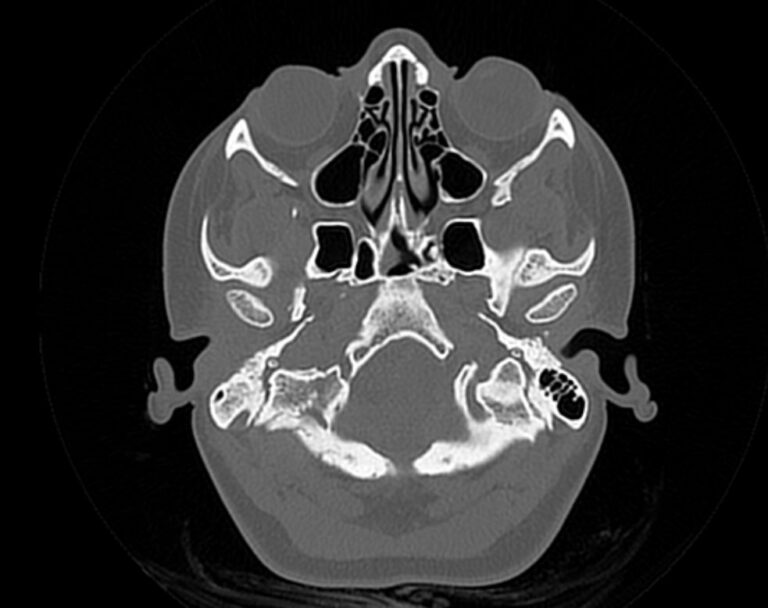

Мультиспиральная компьютерная томография является наилучшим методом диагностики патологии костей черепа. В основе методики лежит использование рентгеновского излучения с последующей цифровой обработкой полученных данных и получения трехмерных реконструкций изображений.

Костная ткань отличается высокой плотностью и способна в большой степени поглощать рентгеновские лучи. Поэтому на послойных снимках, полученных при проведении мультиспиральной КТ черепа можно детально рассмотреть свод черепа, кости лица, основание черепа. Это позволяет с наибольшей точностью визуализировать различные объемные образования, такие как остеомы, дифференцировать фиброзную дисплазию или костные метастазы. Преимуществами методики КТ является отличная визуализация костных структур, быстрота выполнения процедуры и доступная цена. Все это делает КТ незаменимой при диагностике травматических повреждений (например переломов основания черепа или орбит), аномалий развития, при планировании оперативных вмешательств.

Что показывает КТ черепа

- наличие чужеродных предметов;

- скрытые переломы;

- смещение костей;

- опухоли как доброкачественные, так и злокачественные

- нарушенное кровообращение;

- воспалительные заболевания

- метастазы и их локализацию